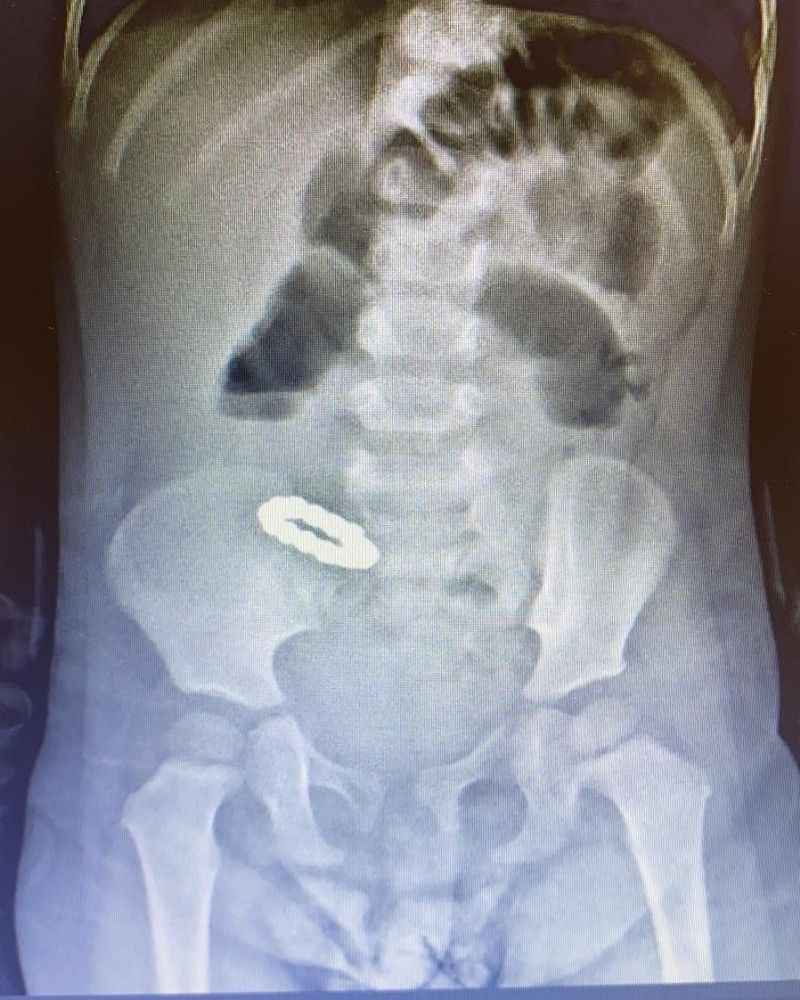

Minik Beren'in getirildiğinde genel durumunun kötü olduğunu belirten Doç. Dr. Özdemir, "Bana bebeğin mıknatıs yutmuş olduğu söylendi. Çektiğimiz karın filminde bilezik şeklini almış küçük yuvarlak mıknatıslar görülüyordu. Hastanın bağırsak tıkanıklığı olduğunu saptadık. Hastanın beslenememesinin nedeni de bu bağırsak tıkanıklığıydı. Ameliyatta ince bağırsakların birkaç yerde birbirine yapışmış olduğunu, ince bağırsakların diğer kısımlarının da bu yapışıklıkların arasına sıkışmış olduğunu gördük. Yapışmış olan bağırsakları birbirinden ayırdığımızda, bu bağırsaklarda 6 adet delik olduğu, bu deliklerden uç uca birbirine tutunmuş küçük mıknatıslar çıktığı görüldü. 12 adet mıknatıs çıkardık. Ama bağırsakta başka mıknatıs kalıp kalmadığından emin olmak için tüm bağırsağı titizlikle tekrar tekrar inceledik. Başka bir mıknatısa rastlamadık. bağırsağın delikler açılmış olan iki bölgesi, 10 cm ve 12 cm'lik parçalar halinde çıkarıldı. İnce bağırsaklar iki bölgeden tekrar birbirine dikilerek bağlandı. Hastamızın bağırsakları 6. günde tekrar çalışmaya başladı. Yemek yiyebilir hale gelen hastamızı, şifa ile taburcu ettik" dedi.